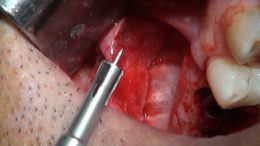

اصول مبانی GBR

+ اساتید گروه علمی بن تاژ پارس (زیرنظر پروفسور غلامی)

- جراحي توسط دکتر عميد از اساتید گروه علمی بن تاژ